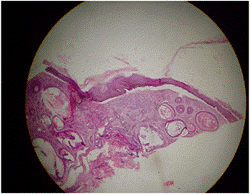

Exámenes realizados: se realiza biopsia de piel (imágenes 5 y 6), confirmándose el diagnóstico de epidermólisis bullosa adquirida, se realiza toma de muestra para inmunofluorescencia directa e indirecta y se inicia tratamiento con colchicina a razón de 1 mg por día, para luego aumentar la dosis según tolerancia de la paciente y evolución de la enfermedad.

Imagen 5. Ampolla subepidérmica, miilios e infiltrado linfohistiocitario en la dermis

Imagen 6. Se observa la ampolla subepidérmica y los quistes de milium